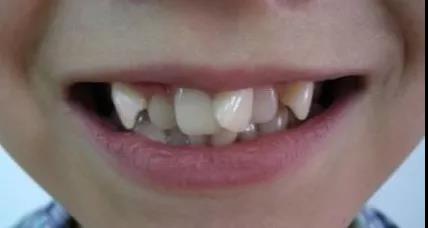

一旦乳牙因为被蛀而提前掉落,留下空隙,后方的恒牙还没有准备好就要“上岗就业”,容易找不准自己的位置,从而长歪长斜

牙齿排列错乱的孩子

宝贝的颜值也会被歪七扭八的牙齿拉低,最重要的是后期还需要通过矫正来恢复正常形态,从而花费一笔不菲的费用。

而对于没有牙缝或者牙缝很小的孩子,换牙后牙齿的生长会受到挤压,可能会导致牙齿偏离原来的生长位置,或者生长畸形。

所以有牙缝很正常,家长们也不要太担心,相反孩子没有牙缝,就需要注意了。